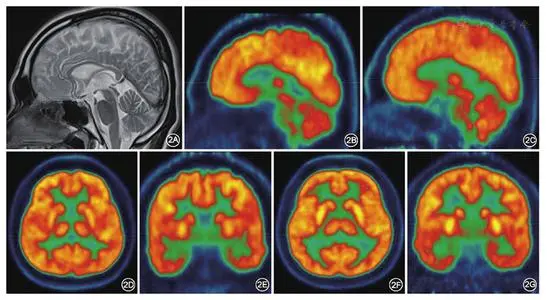

小脑萎缩:通过CT及MR等影像学小脑萎缩诊断可发现脑组织体积减少、脑室扩大 。 如果小脑萎缩可见脑皮质与颅骨板间隙增大 , 大脑沟增宽增深、脑回变平缩小 , 侧脑室及第三脑室扩大 , 侧脑室前后角周围密度减低 。